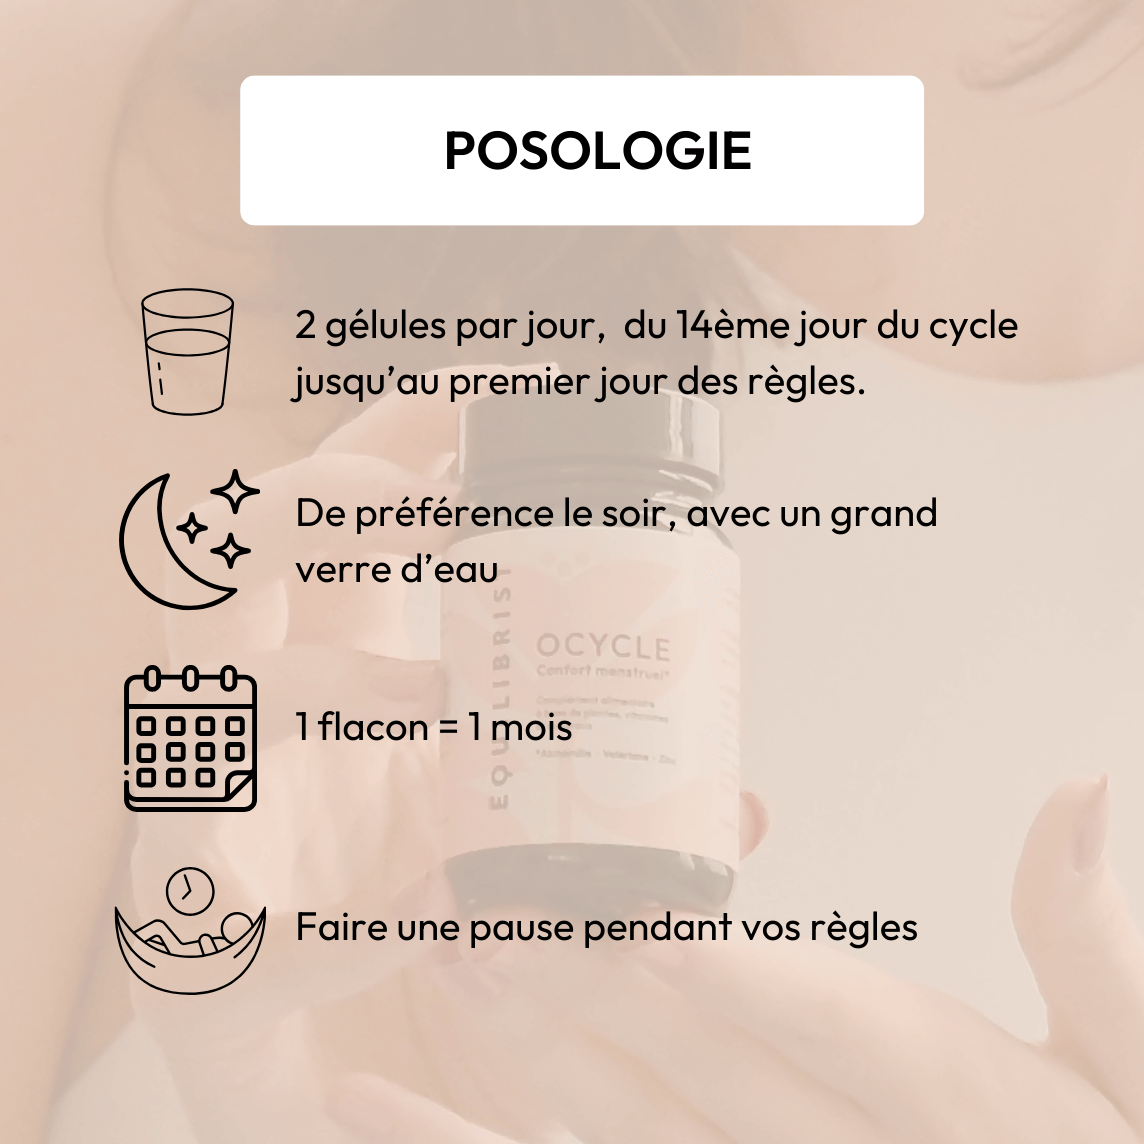

Posologie & conseils d'utilisation

- 2 gélules par jour, à prendre le soir avec un grand verre d’eau, du 14ème jour du cycle (c’est à dire au moment de votre ovulation) jusqu’au premier jour des règles.

- Faire une pause pendant les règles.

- Durée recommandée d’une cure : 3 mois

- Contenance d’un pilulier, 30 gélules, soit 15 jour de cure

Débutez votre cureu du 14ème jour du cycle (c’est à dire au moment de votre ovulation) jusqu’au 1er jour des règles. Faire une pause pendant les règles. 2 gél/jour le soir avec un grand verre d’eau.